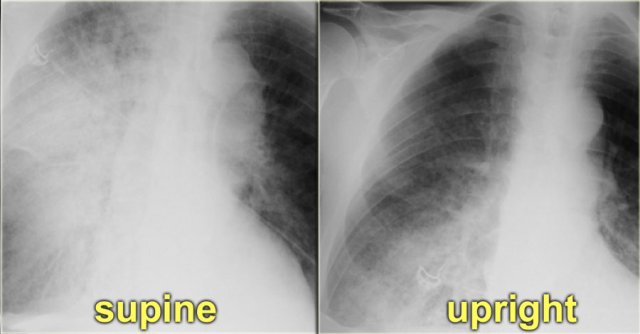

In daily clinical practice many chest films are taken in a supine or semi-erect position and the gravitational difference between the apex and the lung bases will be less.

In the supine position, there will be equalisation of blood flow, which may give the false impression of redistribution.

In these cases comparison with old fims can be helpful.

On the left a patient who first had a chest film in a supine position.

Notice the pulmonary edema, which is almost exclusively seen in the right lung.

A possible explanation for this phenomenon could be, that the patient had been lying on his right side for a while before the x-ray was taken.